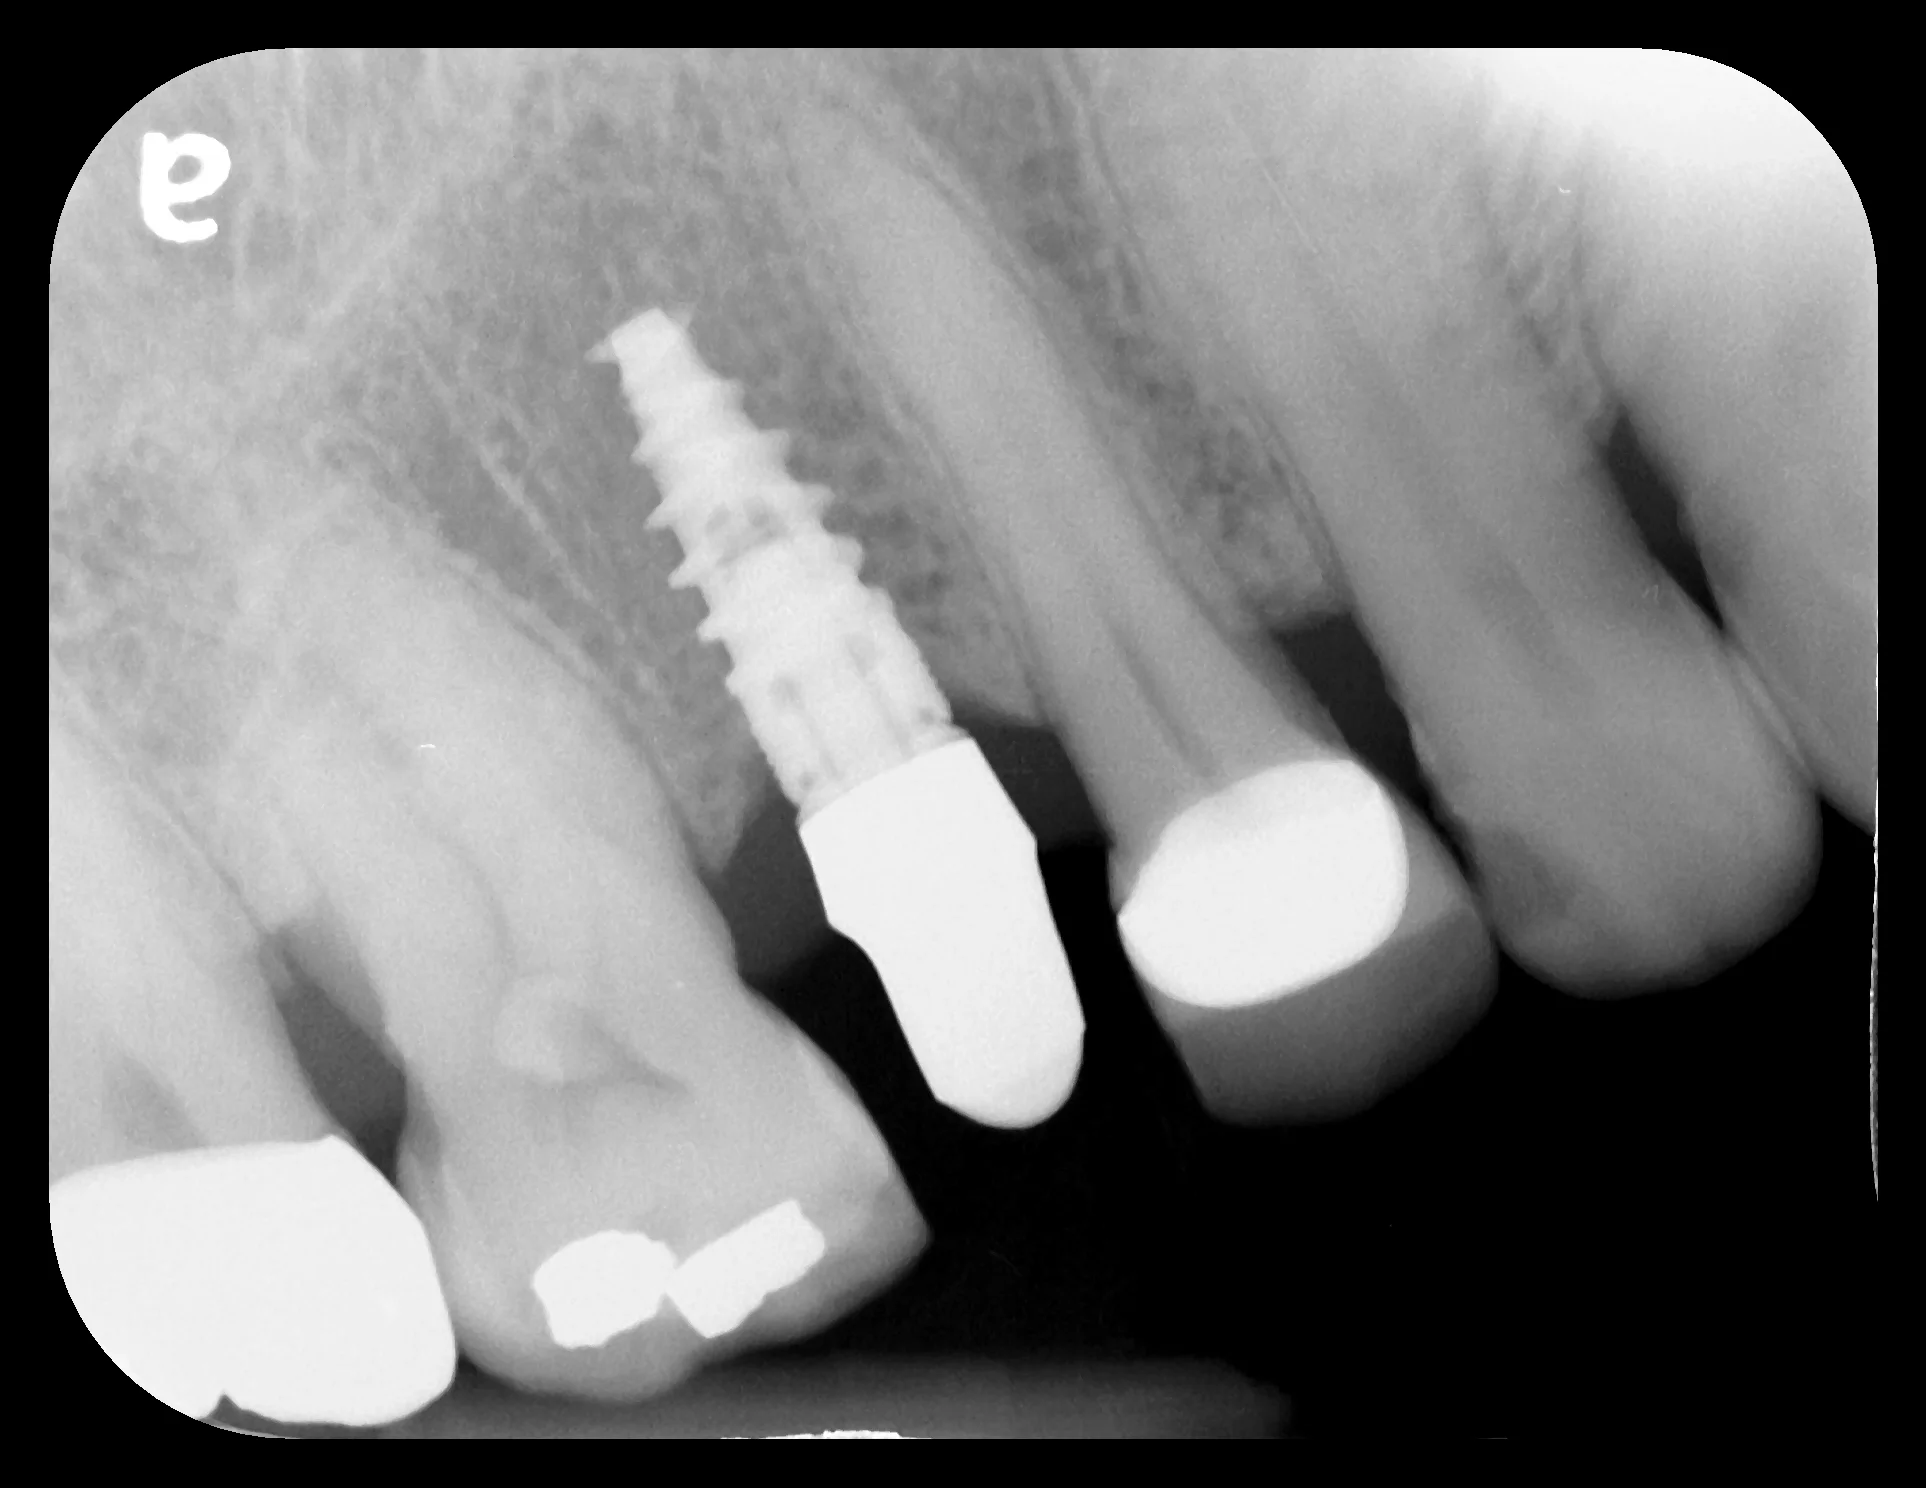

Our patient presented with a crown that popped off. After a thorough exam, our team observed that this tooth had a long history of dental treatments.  A previous doctor performed a root canal, then placed a metal screw inside of the root to hold a metal crown.  Over the years, the tooth became soft from cavities and infected but the patient did not know this was happening because once a root canal is performed, the tooth has no feeling!  Then one day, the crown popped off and she came to our office.  Unfortunately we could not save the tooth and an implant was the best option.  We decided to extract the tooth and perform a bone graft since some of her bone melted away due to tooth infection.  After the bone graft healed, we placed a Nobel Biocare implant then connected her brand new BruxZir porcelain crown to a custom gold abutment!  Our patient is happy and chewing confidently again!